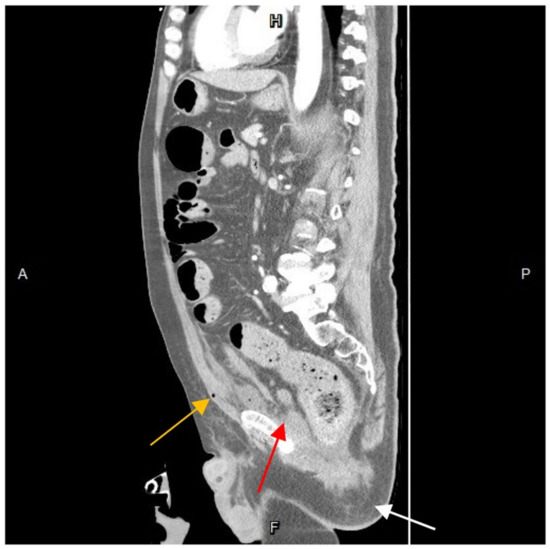

Figure 4. A computed-tomography-guided percutaneous drainage procedure. The arrow demonstrated the direction and position of needle insertion. R, right; L, left; A, anterior; P, posterior.

After resuscitation and blood transfusion, the patient’s vital signs stabilized, and the inotrope support was tapered. The next day, as confirmed by the CT scan and concerned about the further progression of infection, we consulted a radiologist for CT-guided extraperitoneal abscess drainage (Figure 4) and collected a significant amount of turbid fluid. Cultures from the pus were used to identify Klebsiella pneumoniae, Escherichia coli, Viridans streptococcus gr., and Bacteroides fragilis. Subsequently, antibiotic treatment with piperacillin-tazobactam was prescribed accordingly.

In retrospect, given the spreading abscess noted around the bladder via CT scan and fluctuating blood pressure levels, diagnostic laparotomy over the lower abdomen should have been considered. However, during an emergent CT scan conducted following an episode of anal bleeding, a progressed extraperitoneal abscess was identified, located anteriorly to the bladder. It was also reported that after the primary incision, early recurrence was seen as a major risk factor for abscess expansion, leading to worse outcomes [5]. Accordingly, secondary intervention should involve more thorough and adequate strategies. Nevertheless, at this point, the abscess was primarily contained in the extraperitoneal space without causing extensive invasion leading to systemic instability. The radiologist also suggested that the pre-vesical abscess was approachable and drainable. Consequently, based on previous experience and the radiologist’s suggestion, percutaneous drainage was selected as the intervention and was successfully performed.